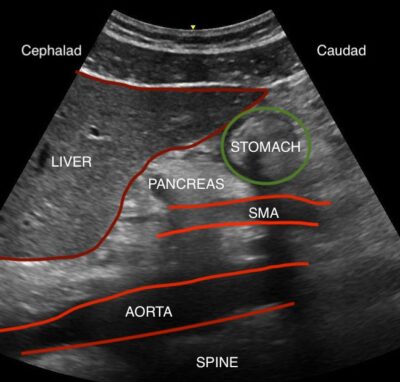

Course work includes physics, cross-sectional anatomy, abdominal, introductory vascular, and obstetrical/gynecological sonography. Competencies are attained in identification of normal anatomy and pathological processes, use of equipment, fetal growth and development, integration of related imaging, and patient interaction skills.

The Medical Sonography curriculum provides knowledge and clinical skills in the application of high-frequency sound waves to image internal body structures.